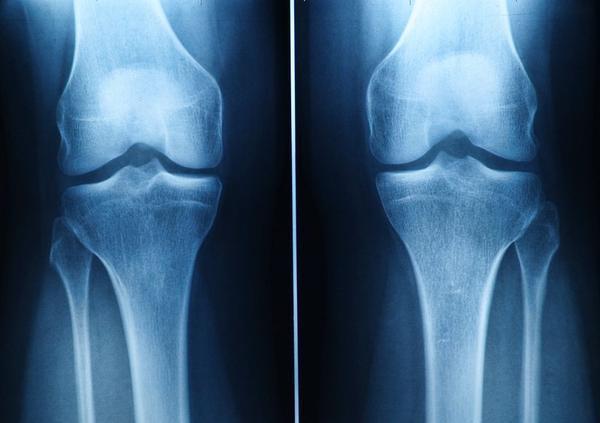

3、膝关节压力增大

相信很多人在跷二郎腿的时候 , 都能感受到膝关节的压力在增大 , 有的还会表现出膝盖疼痛的症状 。 这是因为在跷二郎腿时 , 膝盖是扭曲的 , 这就会导致膝盖局部经受压迫 , 进而还可能出现膝关节疼痛的症状 。

尤其是对于那些中老年人来说 , 这样做的话就会使膝关节的磨损加重以及膝关节的退行性变加速 。